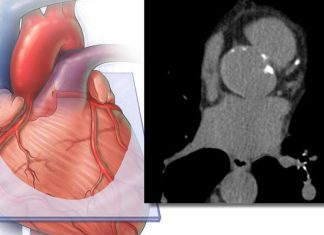

Atrys Health y Siemens Healthineers se asocian para integrar tecnología de...

Portal Red Salud | Grupo Prensa Digital | isa

-

noviembre 11, 2025

0